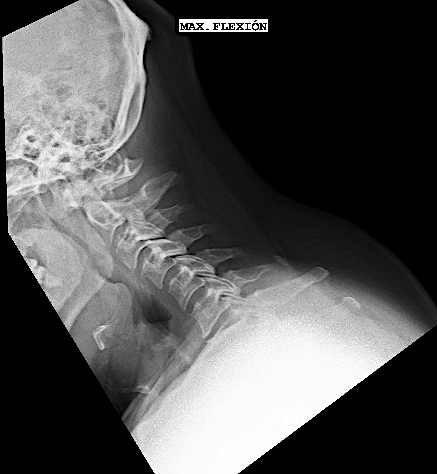

- a las peculiaridades anatómicas de la región: el mediastino anterior con los grandes vasos dificulta el acceso a la columna (inclusive a cirujanos torácicos y cirujanos vasculares). El abordaje clásico cervical puede requerir en los niveles más altos (Th1 y Th2) una esternotomía con osteotomía de clavícula y reconstrucción posterior. Generalmente, el cálculo del ángulo Thoracic Inlet Angle (TIA) puede predecir si será un abordaje más o menos dificultoso (para discos cervicales bajos o Th1-Th2 con TIA >60º). En estos casos, suelo informar al paciente la posibilidad de esternotomía (o completar con abordaje posterior la resección) y para el día de la intervención solicito la colaboración de un cirujano torácico. El abordaje posterior es mucho más sencillo, sin embargo plantea como principal dificultad técnica la imposibilidad de descomprimir el canal central en su sector anterior. Otro inconveniente a tener en cuenta en la elección de la vía posterior es la potencial secuela de cifosis secundaria a la resección de elementos de estabilidad posteriores (músculos, ligamentos, huesos), probable causa de dolor cervicotorácico mecánico.

Por las razones expuestas, a pesar de un thoracic inlet angle bastante alto, opté por realizar un abordaje anterior con descompresión + artrodesis IS con cajas atornilladas C7-Th1.